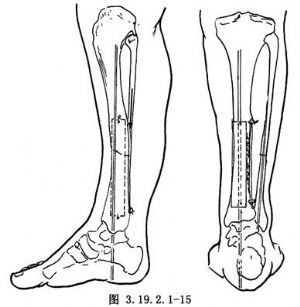

11.5 5.內固定

若脛骨遠端較長,可於脛骨遠端骺板上方1.25~2cm處和脛骨近側段橫行穿入斯氏針,用Charnley加壓器固定,保持脛骨兩斷端牢固嵌壓和良好對位(圖3.19.2.1-14)。若脛骨遠端短小,可用較粗的斯氏釘逆行法髓內固定脛骨。先從脛骨遠斷端向遠側打入斯氏釘,穿過脛骨遠端骨骺中心、踝關節、距下關節,從跟骨蹠面穿出,然後對正脛骨遠、近端,將斯氏釘打進脛骨近端,其理想的穿釘方向應使釘的近端恰在脛骨後側皮質。遠側釘尖埋於皮下(圖3.19.2.1-15)。